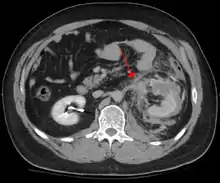

Blunt abdominal trauma

Blunt abdominal trauma (BAT) represents 75% of all blunt trauma and is the most common example of this injury.[4] 75% of BAT occurs in motor vehicle crashes,[5] in which rapid deceleration may propel the driver into the steering wheel, dashboard, or seatbelt,[6] causing contusions in less serious cases, or rupture of internal organs from briefly increased intraluminal pressure in the more serious, depending on the force applied. Initially, there may be few indications that serious internal abdominal injury has occurred, making assessment more challenging and requiring a high degree of clinical suspicion.[7]

When blunt abdominal trauma is complicated by 'internal injury,' the liver and spleen (see blunt splenic trauma) are most frequently involved, followed by the small intestine.[9]

In most settings, the initial evaluation and stabilization of traumatic injury follows the same general principles of identifying and treating immediately life-threatening injuries. In the US, the American College of Surgeons publishes the Advanced Trauma Life Support guidelines, which provide a step-by-step approach to the initial assessment, stabilization, diagnostic reasoning, and treatment of traumatic injuries that codifies this general principle.[9] The assessment typically begins by ensuring that the subject's airway is open and competent, that breathing is unlabored, and that circulation—i.e. pulses that can be felt—is present. This is sometimes described as the "A, B, C's"—Airway, Breathing, and Circulation—and is the first step in any resuscitation or triage. Then, the history of the accident or injury is amplified with any medical, dietary (timing of last oral intake) and history, from whatever sources such as family, friends, previous treating physicians that might be available. This method is sometimes given the mnemonic "SAMPLE". The amount of time spent on diagnosis should be minimized and expedited by a combination of clinical assessment and appropriate use of technology,[32] such as diagnostic peritoneal lavage (DPL), or bedside ultrasound examination (FAST)[33] before proceeding to laparotomy if required. If time and the patient's stability permits, CT examination may be carried out if available.[34] Its advantages include superior definition of the injury, leading to grading of the injury and sometimes the confidence to avoid or postpone surgery. Its disadvantages include the time taken to acquire images, although this gets shorter with each generation of scanners, and the removal of the patient from the immediate view of the emergency or surgical staff. Many providers use the aid of an algorithm such as the ATLS guidelines to determine which images to obtain following the initial assessment. These algorithms take into account the mechanism of injury, physical examination, and patient's vital signs to determine whether patients should have imaging or proceed directly to surgery.[9]